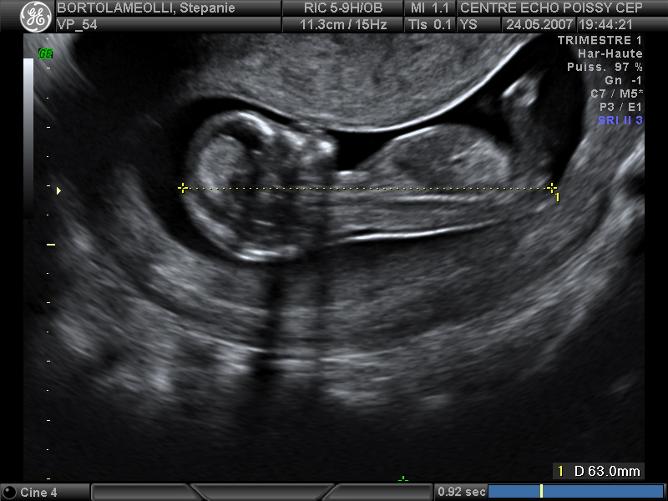

Echographies